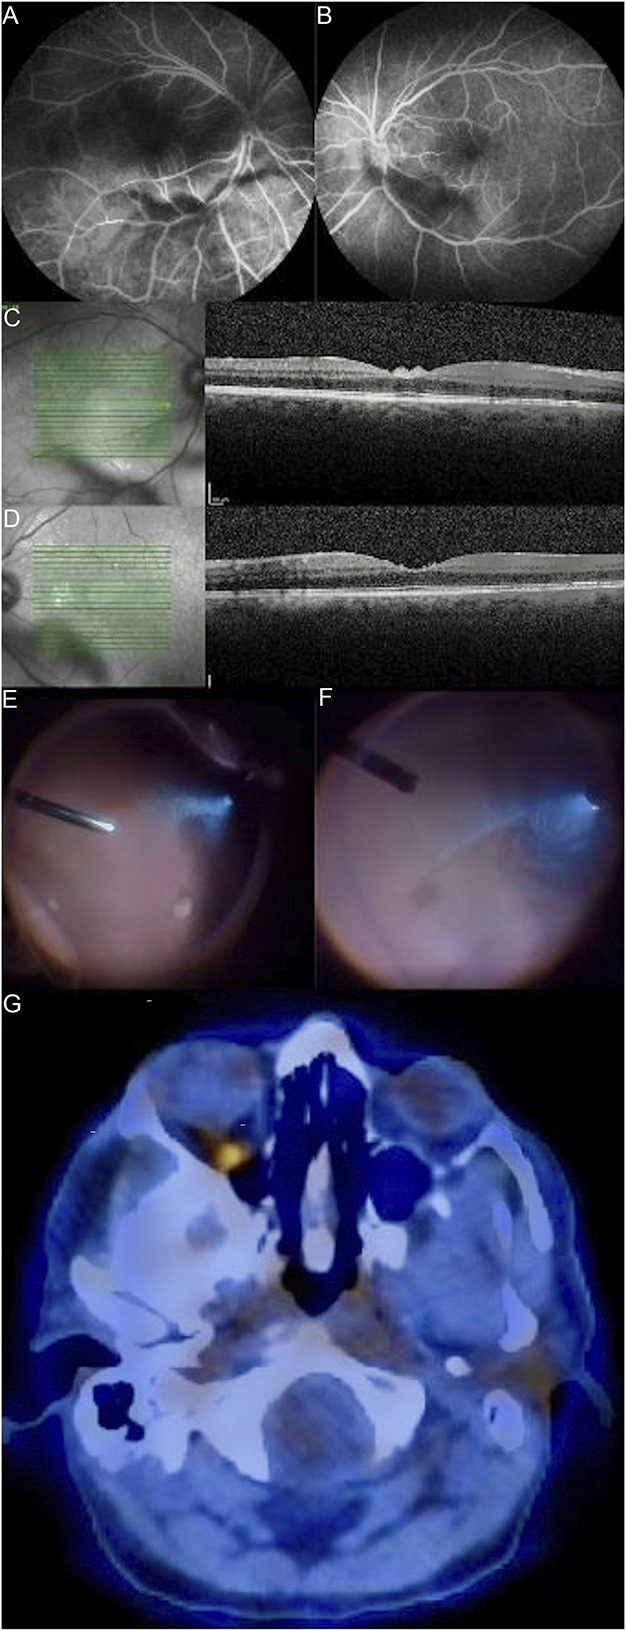

伪装成难治性葡萄膜炎的原发性玻璃体视网膜淋巴瘤--顺其自然吧。

Primary vitreoretinal lymphoma masquerading as refractory uveitis-just go with the flow.